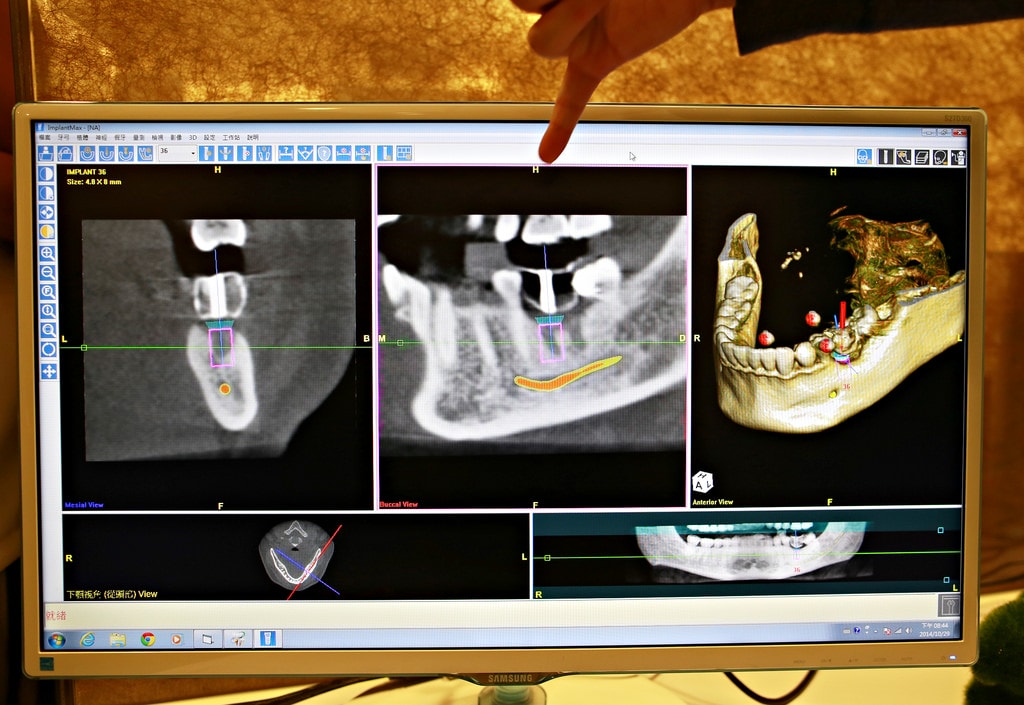

這台植牙導航系統讀取3D-CBCT資訊,顯示顎骨、齒槽骨神經、鼻竇腔的立體生理結構圖像

邊操作的時候旁邊的螢幕就會同步顯示喔(就是下面這個圖示)

主要是在替病患植牙前先進行模擬的植牙手術,利用導航系統電腦3D定位可以讓植牙位置、深度、角度更加精準

結合以上這兩台機器可以節省非常多時間且增加植牙的成功率囉!!!